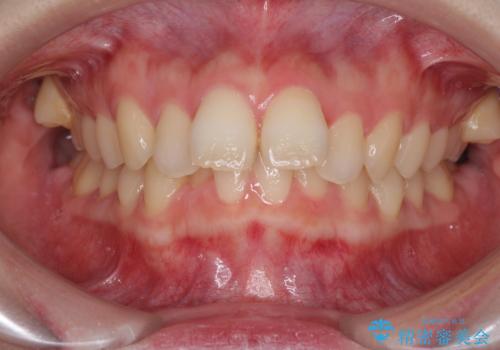

- 口元の突出感を気にして来院された患者様です。

左右ともに上顎奥歯が外を向き、下顎奥歯が内側に倒れているシザーズバイトであったため、補助装置により改善することとしました。

上下の咬み合わせは、下顎に対して上顎が相対的に前方にあったため、奥歯のシザーズバイト改善後に上顎左右第一小臼歯2本を抜歯し、上顎前突を改善していくこととしました。